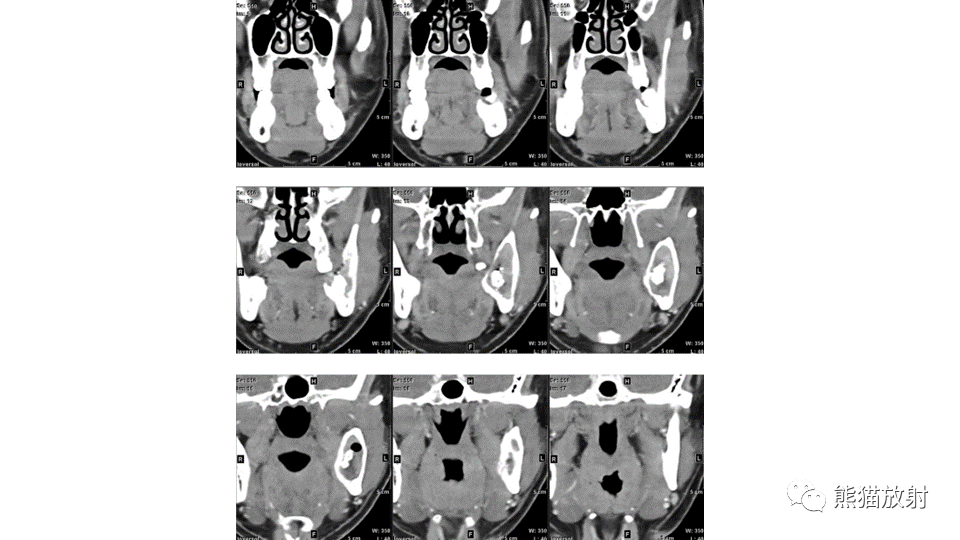

【病例】下颌骨成釉细胞瘤2例CT-4

【病例】下颌骨成釉细胞瘤2例CT-5

【病例】下颌骨成釉细胞瘤2例CT-6

【病例】下颌骨成釉细胞瘤2例CT-7